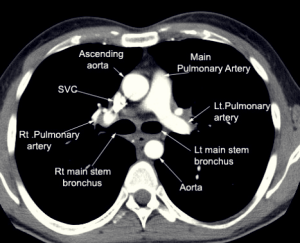

흉부외과는,

가슴에 위치하는 심장,폐,기관,식도,대동맥,흉벽,종격동,횡격막,늑막 등을 진료하는 전문 진료 분과입니다.